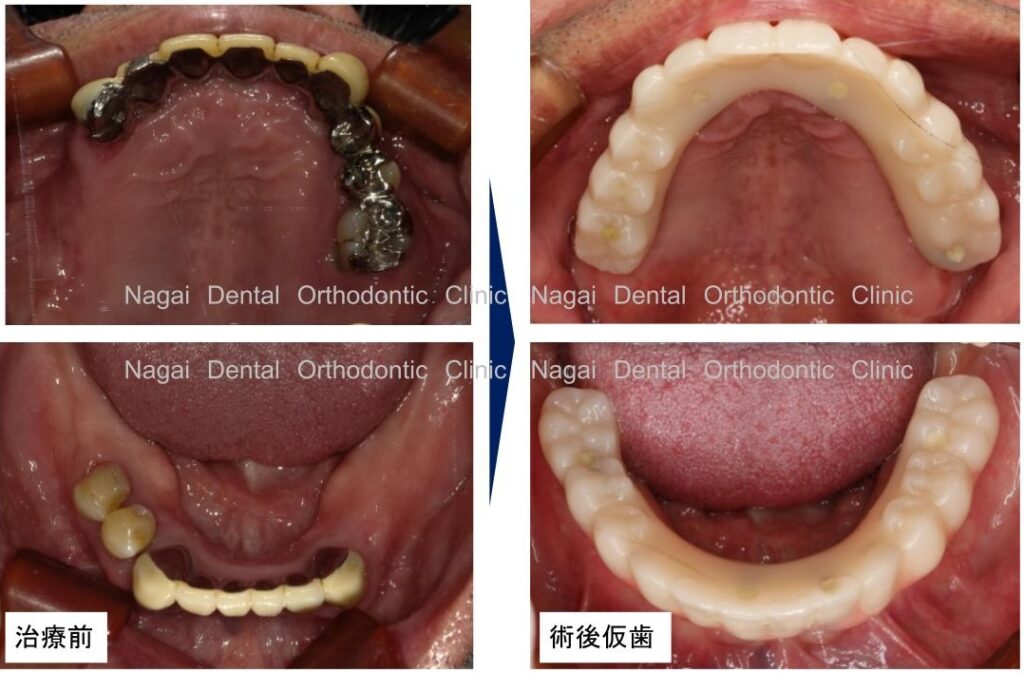

【口腔内の詳細変化】

▲再構築を目的とした治療を行いました

▲欠損していた左上奥歯部分の補綴完了状態

▲支持の安定が期待される治療を行いました

| 治療内容 | 上顎:オールオン4 |

|---|---|

| 年齢/性別 | 30代/男性 |

| 背景 | 多数歯欠損と咬合崩壊を主訴に来院。上顎は骨造成を回避し即日回復を目指したオールオンフォー、下顎は臼歯部インプラントによる再構成を選択しました。チタンフレームとジルコニアで耐久性と審美性を両立。術後は適切な噛み合わせにより咀嚼能率が向上し、機能・審美面ともに満足度の高い日常生活を取り戻されています。 |

| 治療期間 | 約5か月(通院8回) |

| 費用 | 5,384,400円(税込み) |

| リスク/副作用 | インプラント手術は全身状態や持病によっては適応できない場合があります。また、術後の口腔清掃を怠ると、天然歯の歯周病に似たインプラント周囲炎が起こる可能性があるため、定期的なメンテナンスが必要です。 |